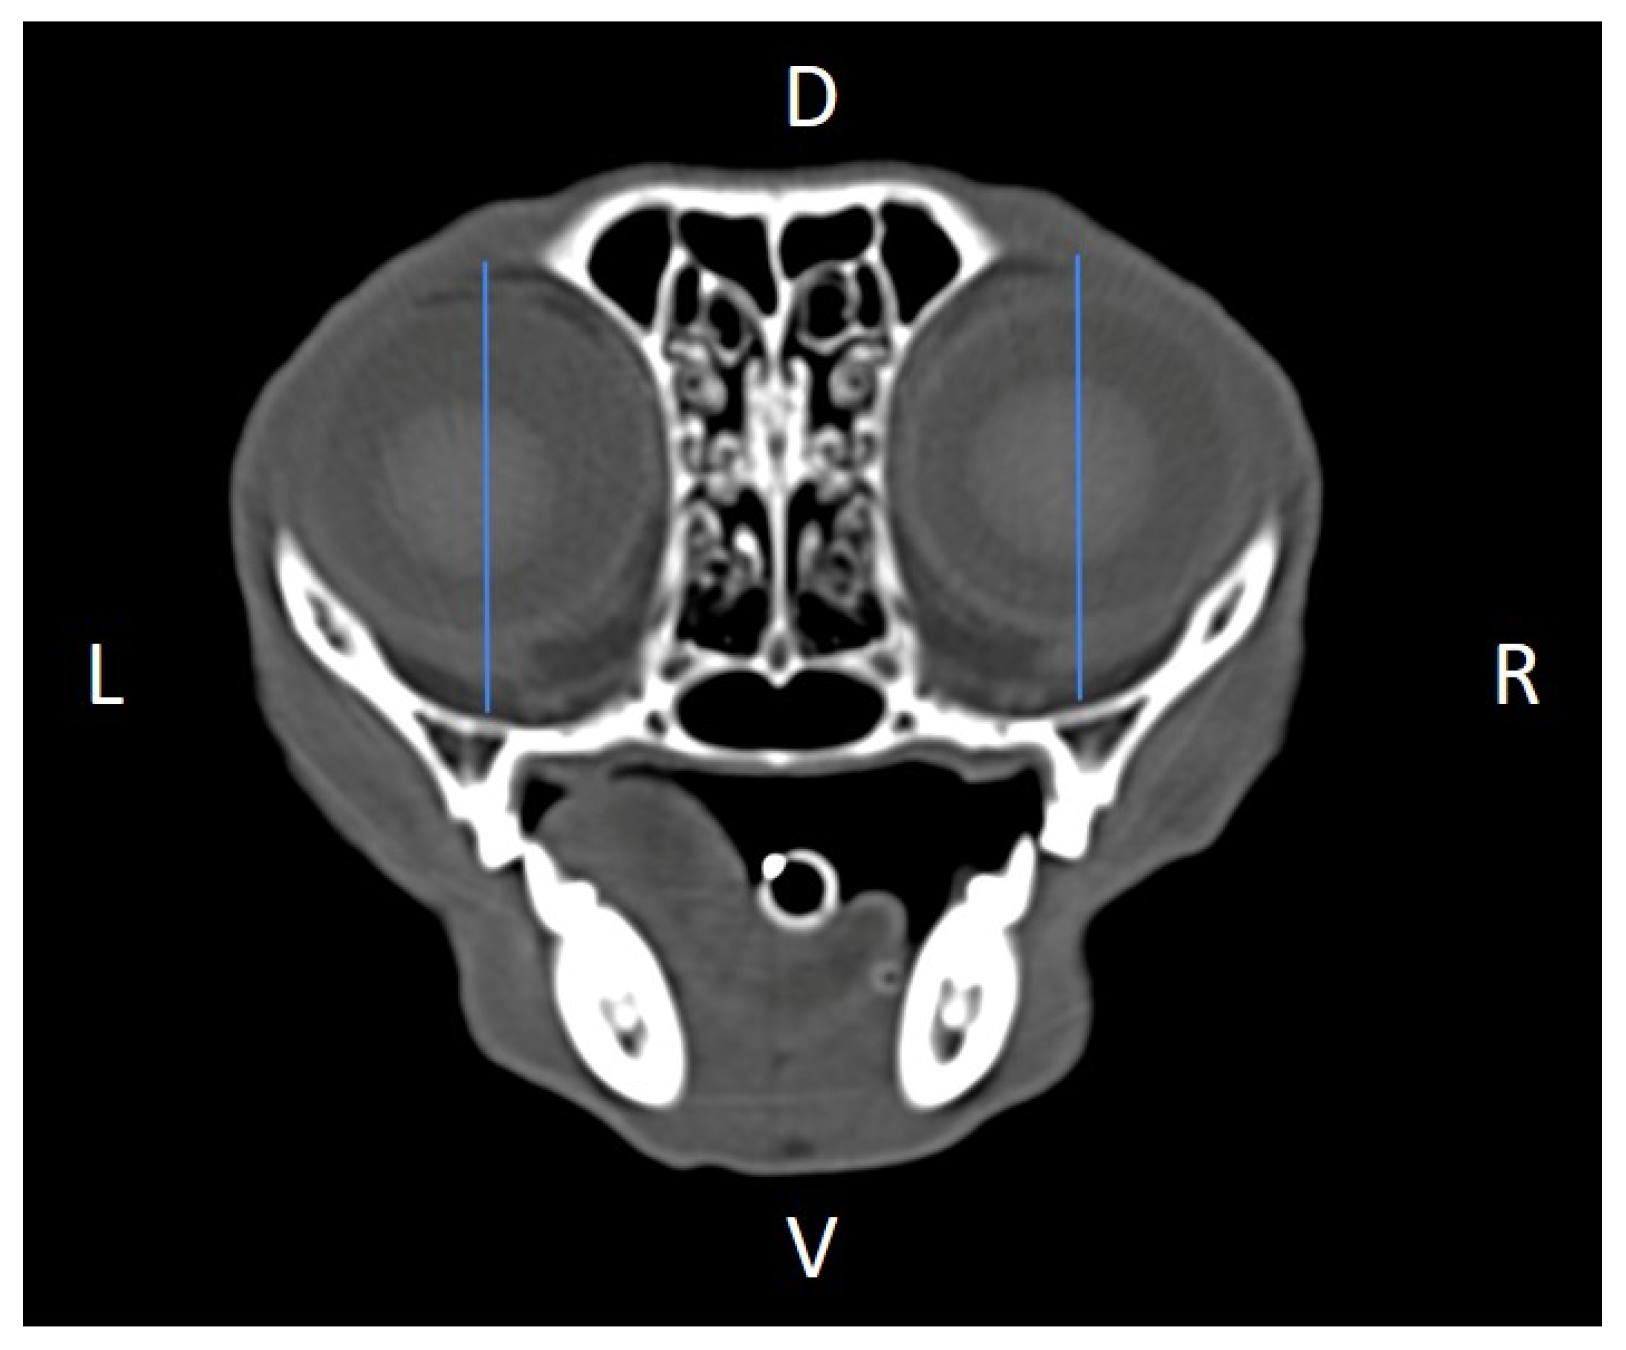

Linear morphometric parameters (Table 1) were obtained directly from CT images using HorosTM v3.3.6.dmg DICOM software with bone filters. Prior to measurement, all images were calibrated from pixels to millimeters. A preliminary study and prior training were conducted, to establish anatomical landmarks that would allow for the repeatability of the measurement methodology by J.F.R., A.R.S., S.A.-P. Recorded variables included infraorbital foramen major axis (Figure 2), minor axis (Figure 3) and length (Figure 4), distance between infraorbital foramina (DIF) (Figure 5), orbital height and width (Figure 6 and Figure 7), zygomatic arch width (Figure 8), skull width and length (Figure 9). Ratios were calculated to normalize for skull size. As preliminary results revealed adequate repeatability of measurements, and in order to reduce the analysis margin of error, two measurements of each studied parameter were performed. The measurements were performed by the same operator (to reduce interpersonal errors), and each measurement of each parameter was performed at different times, in order to reduce intrapersonal errors. Then, the arithmetic mean of the measurements was calculated.

Figure 2. Infraorbital major axis (IFMA) measured at the left and right sides, on a transverse CT image (blue lines). D, dorsal, L, left, R, right, V, ventral.